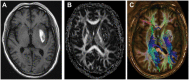

Figures